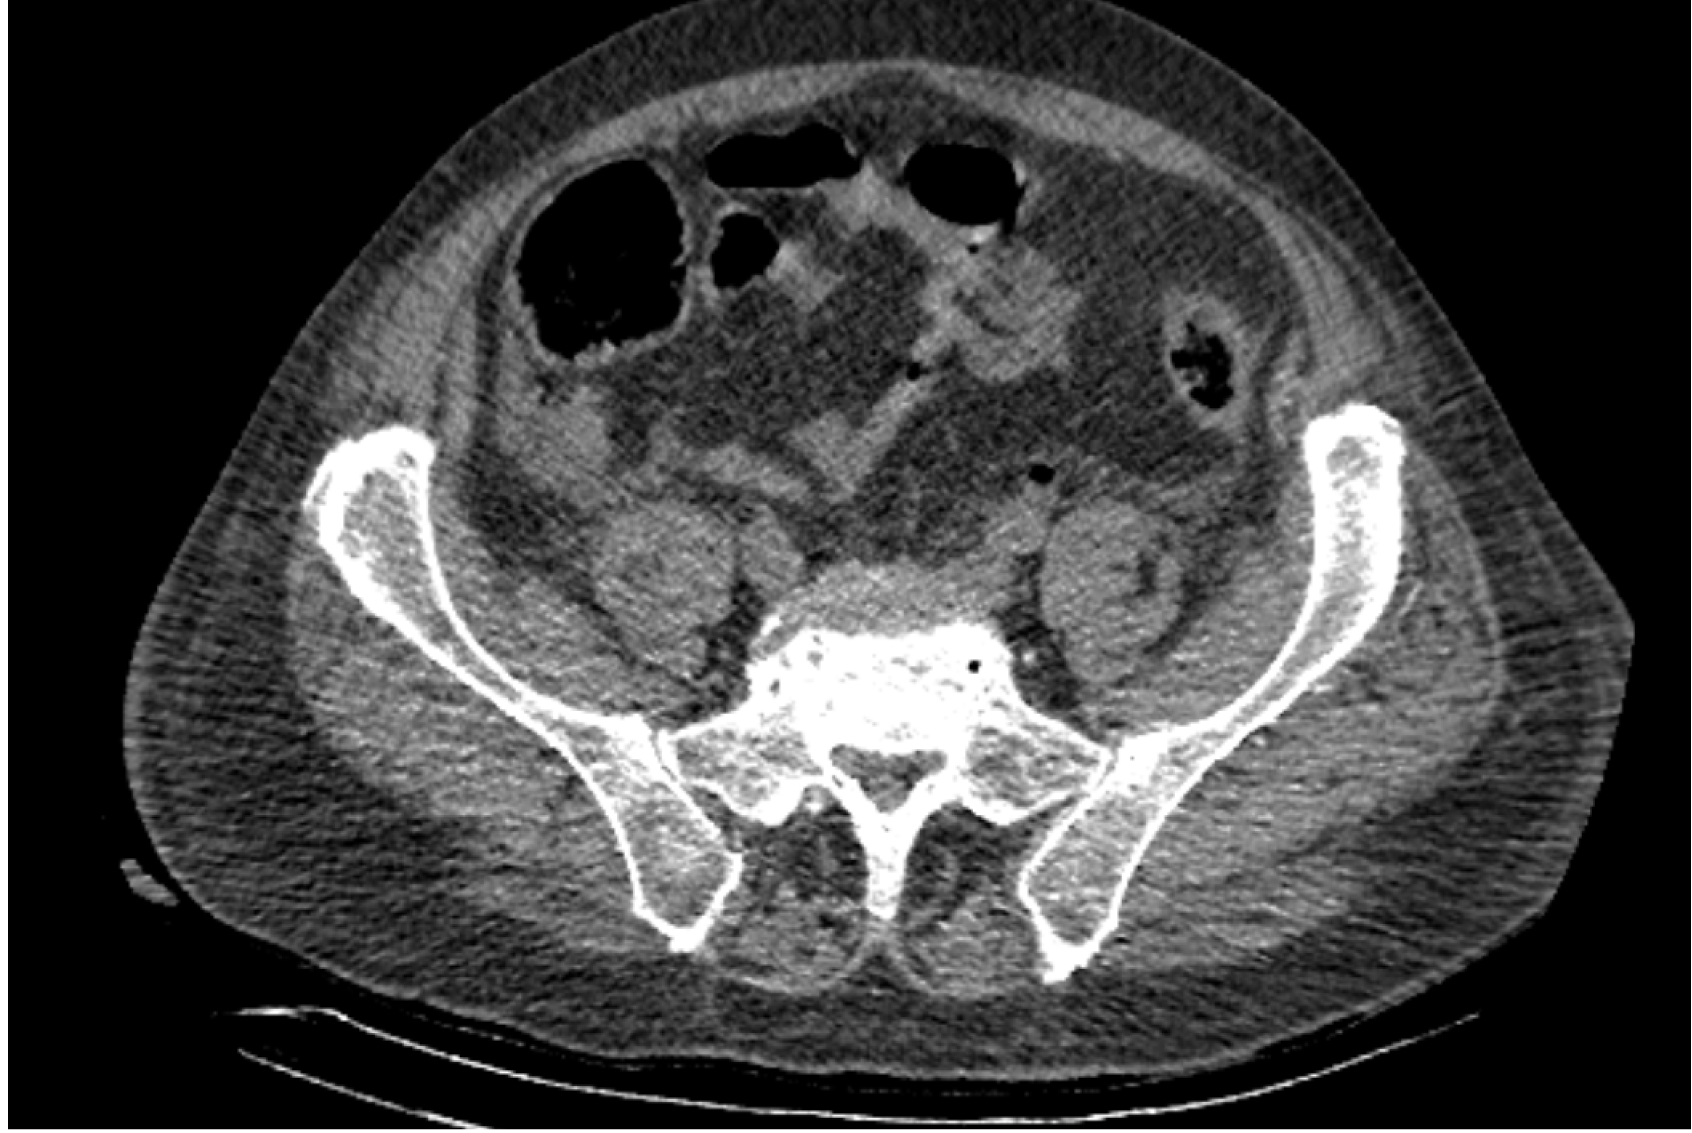

На следующий день состояние пациента оставалось тяжелым, с отрицательной динамикой, креатинин сыворотки возрос до 735,2 ммоль/л, Появились жалобы на слабость, тошноту. При осмотре: живот мягкий, вздут по всем отделам, при пальпации болезненный. Область почек не изменена, при пальпации безболезненна, патологических изменений в области почек не выявлено. Симптом поколачивания отрицательный билатерально. При УЗИ были обнаружены плевральный выпот по 300–400 мл с каждой стороны, гепатомегалия, увеличение размеров селезенки, асцит. Кроме того, в обеих почках были визуализированы тени, характерные для конкрементов. По данным компьютерной томографии (КТ) конкрементов не обнаружено, но в лоханке, на всем протяжении левого мочеточника и, частично, в правом мочеточнике, а также в мочевом пузыре визуализировался газ (рис. 1–6).

Рис. 1. Компьютерная томография органов брюшной полости, забрюшинного пространства, органов малого таза. Газ в мочевом пузыре

Рис. 2. Компьютерная томография органов брюшной полости, забрюшинного пространства, органов малого таза. Газ в мочевом пузыре